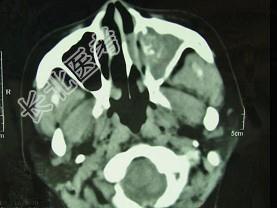

- 单项选择题男,41岁, 左侧鼻腔胀痛半年余,CT检查如图, 最可能诊断为 ( )

A、出血坏死性息肉

B、化脓性鼻窦炎

C、变应性鼻窦炎

D、真菌性鼻窦炎

E、上颌窦癌